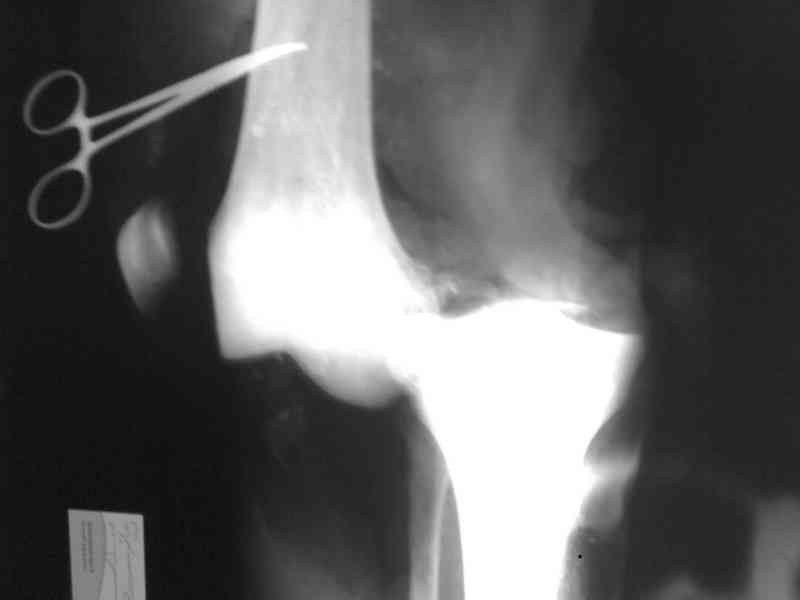

Bolnoi 27 let, DTP, Motorcycle trauma, postupil v kreane tiajelom

sostoianii, osnovnia trauma- otkrity totalny vyvih levogo kolennogo

sustava s povrezhdeniem malogo bertsovogo nerva, trakcionnot povrezdenie

podkolennoi arterii bez narushenia tselostnost' sosuda, pomosh' okazana

v nujnum obeme, kakoe ze mnenie uvazaemih kolleg naschet dalneshego

vedenia bolnogo?